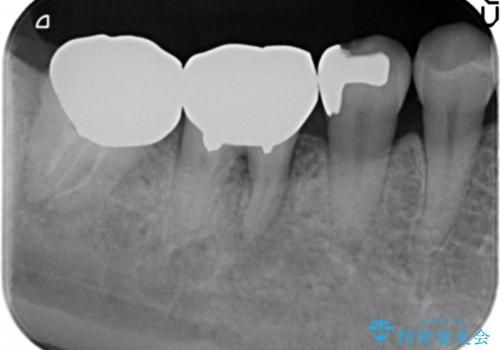

根管治療 → リトリートメント

金属をセラミックにしたい、根管治療も行ったケース

根管治療の注意事項(リスク・副作用など)

- 根管治療により類似の全ての症例の問題が解決するわけではなく、症例はあくまでも一例です

- 根管治療により痛みや腫れがひかない事や、術後に痛みや腫れが生じる事、治療によるファイル破折やパーフォレーションなどの偶発症、術後の歯根破折を生じる可能性もあります